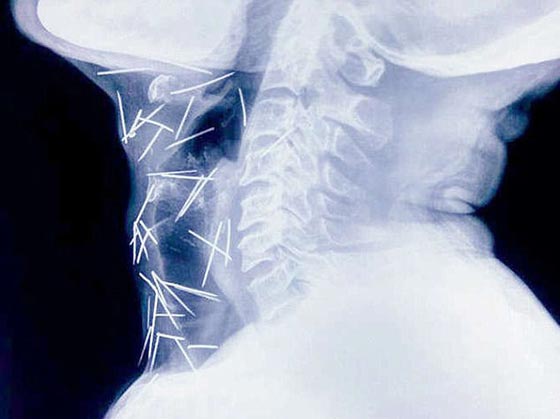

أما آخر حالة حيّرت الأطباء لدى عثورهم على عشرات الدبابيس المغروزة في مختلف أنحاء جسد رجل لا يعرف كيف وصلت هناك! واضطر الهندي بدريلال مينا، البالغ من العمر 56 عاماً، إلى زيارة ستة مستشفيات والخضوع لثلاث عمليات جراحية لاستخراج الدبابيس المغروزة في ذراعيه وقدميه وعنقه. ووفقاً لتقارير الأطباء، أزيل حتى الآن 91 دبوساً، وكان بعضها صدئاً جداً لوجوده هناك لأكثر من ستة أشهر.

ويقول الدكتور لاليت موهان باراشار، الذي أجرى العملية لمينا، "كان إخراجُ الدبابيس بأمان أمراً في غاية الصعوبة، حيث إن بعض الدبابيس كان موجوداً في القصبة الهوائية، والمريء، وحتى في الشريان السباتي الذي يحمل الأكسجين إلى الدماغ". لكن مينا يُصرّ على أنه لم يغرزها بنفسه، ويدعي أنه ليس لديه فكرة عن كيفية دخولها إلى جسده. وكان مينا في بداية الأمر، قد ذهب إلى مستشفى خاص وهو يشكو من آلامٍ في القدم ومن داء السكري؛ ولكن الأطباء وجدوا 75 دبوساً في أجزاء مختلفة من جسده، فيما وجد المعهد الآسيوي للعلوم الطبية في فريداباد (AIMS) - الذي تبنى حالة مينا- 75 دبوساً آخر. ويوضح المعهد أن المهمة الأكثر صعوبة هي "إزالة تلك الدبابيس التي اخترقت الأعصاب الحيوية والشرايين والأعضاء، مثل المريء والشريان السباتي الذي يزود الدم بالدماغ". وأذهل ازدياد عدد الدبابيس الأطباء، لا سيما وأن مينا يُصرُّ هو وأسرتُه على أنه لم يغرز نفسه بهذه الدبابيس، فيما أوصت سلطات المستشفيات بإجراء تقييم نفسي له بعد تعافيه.